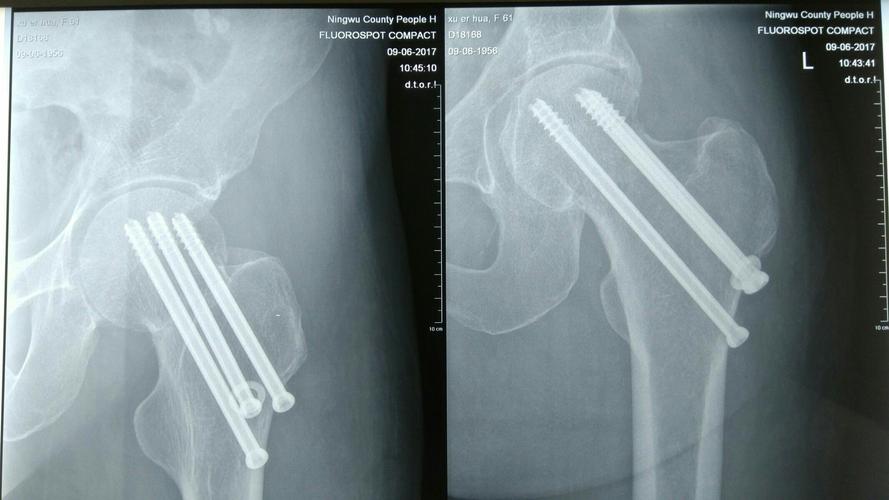

目前股骨颈骨折内固定最常采用 3 根空心钉固定,空心钉在股骨颈内 的空间构型要遵循平行分散和三点固定原则 。传统手术的进行需术者在术中透视下完成空心钉的置入,不仅操作难度高,且对术者手术技巧要求高,难以保证将空心螺钉置入理想方向与位置,

且股骨颈直径较小,徒手置钉常出现髓内钉穿出骨皮质或穿入关节腔内,因此常需多次钻孔及透视, 上述操作将会对患者产生二次伤害 ,增加了螺钉松动、骨折移位及骨折不 愈合等不良后果发生的几率。

而骨科机器人可通过 C 臂机获取患者信 息,并建立完整精确的三维信息,从而辅助术者在术前或术中设计手术方案,并由机器人完成空间位置配准 ,在术中将放置手术工具(如钻头、铣 刀等)精确放置于相应手术部位.

在定位精确不足时还可通过光学捕捉系 统进行精度补偿,从而为术者提供准确安全的螺钉通道 ,在骨科机器人已 钻削好的唯一通道中,术者可自主控制完成高精确度的内固定螺钉的置入。

Liebergall等发现, 在计算机导航手术系统辅助下进行股骨颈骨折空心钉 内固定,其空心钉空间构型的平行分散度优于传统手术组,且螺钉穿出股 骨头及股骨头坏死等并发症的发生率也较传统手术组低。

这是因为一方面, 机器人辅助手术在螺钉平行度、术中 X 线线透视次数及总时间、导针钻孔 次数、空心钉置入后更换次数、置入空心钉所需时间、出血量等指标方面 均优于传统手术组,更有利于患者术后的髋关节功能恢复;

另一方面,机 器人组在随访期内伤口感染、骨折不愈合、内固定松动、骨折移位、股骨 头坏死等并发症方面也优于传统手术组导航及手术机器人辅助下完成的手术不仅能尽可能减少股骨颈骨折内 固定的术中透视次数,还能最大限度的提高空心钉放置的准确度。